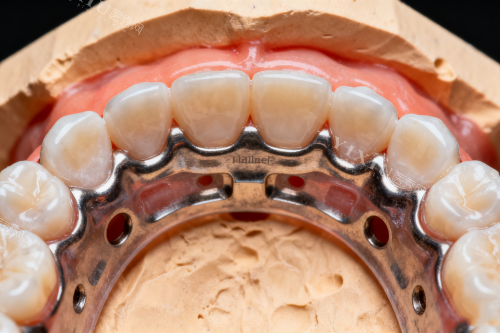

玖蕴口腔特别值得称道的是其不断更新的治疗设备。诊所定期引进新的诊疗技术,在牙齿种植和矫正领域有着明显优势。一位在这里完成全口种植的中年患者评价说:"医生解释得很详细,整个过程没有不适感,现在吃东西完全没问题。"

种植牙对医生技术要求较高,不妨多比较几家诊所的方案,了解所使用种植体品牌及医生相关资质。